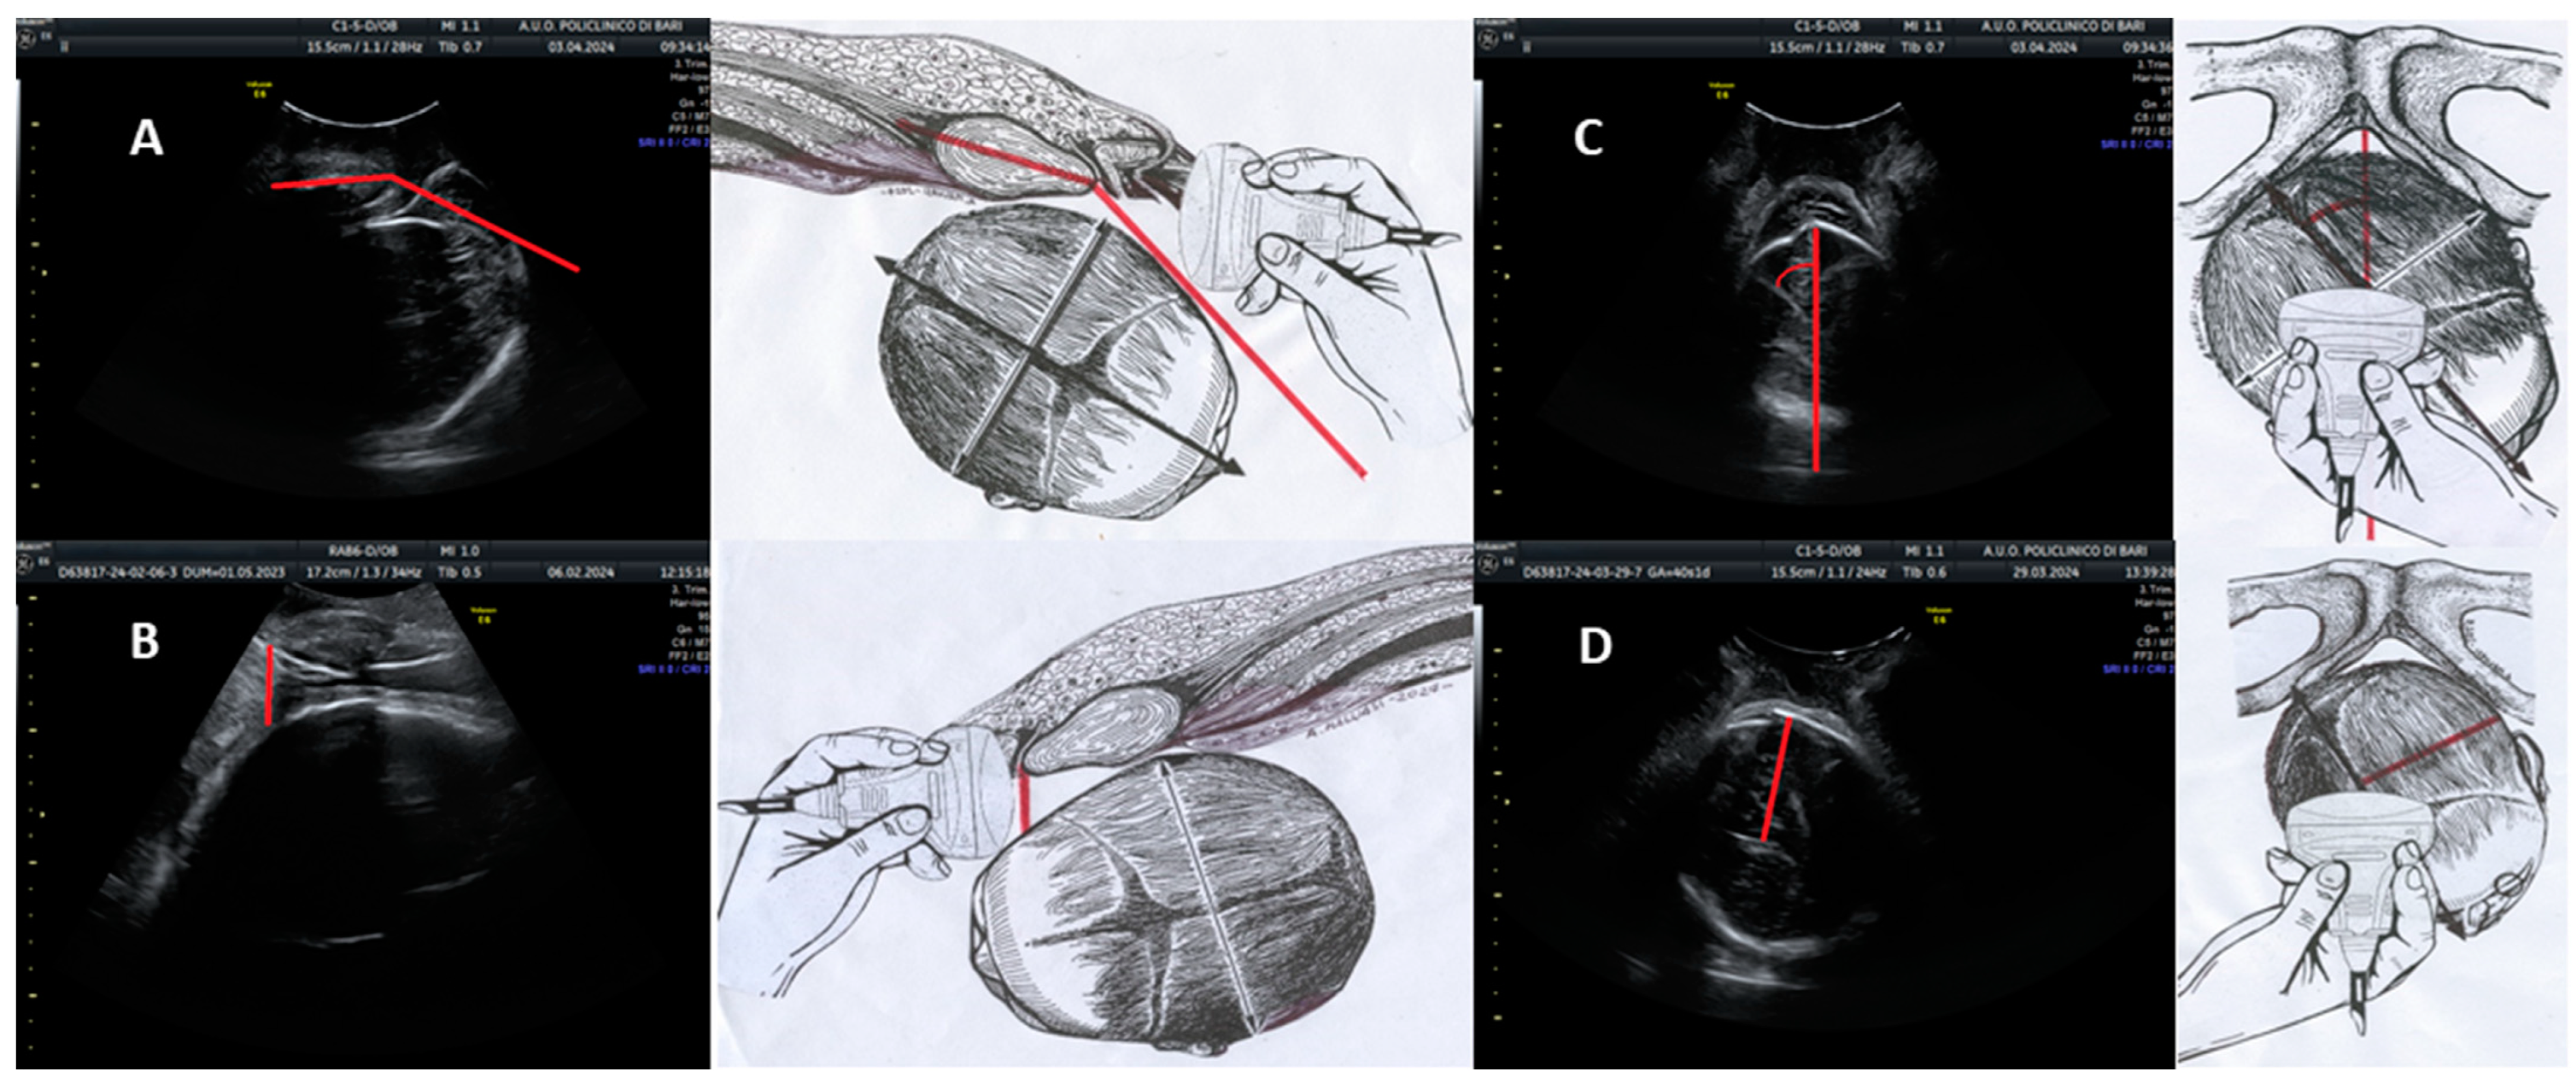

The angle of progression (AoP) is defined as the angle formed by a line passing through the midpoint of the pubic symphysis and a tangent to the fetal skull, as visualized on a longitudinal ultrasound scan. In Figure 1A, the schematic representation on the right and the corresponding ultrasonographic image on the left depict a longitudinal scan employed to evaluate the AoP. The red line demarcates this angle, with the fetal head positioned in the occiput anterior orientation.

Ultrasound parameters for intrapartum assessment of fetal head progression and position. (A) Angle of progression (AoP): longitudinal scan showing the AoP (red line) with the fetal head in the occiput anterior position. (B) Fetal head–symphysis distance (HSD): sagittal ultrasound section aligned with the HSD along the infrapubic line (red line), with the fetal head in the occiput anterior position. (C) Midline angle (MLA): Transverse probe placement parallel to the bi-ischial line; ultrasound image shows the MLA (red angle) with the fetal head in the right occiput anterior position. Midline visible as an echogenic line between the cerebral hemispheres; the red line indicates the infrapubic line. (D) Asynclitism degree (AD): Transverse scan; the ultrasound image demonstrates AD measurement with the fetal head in the right occiput anterior position, showing anterior asynclitism. The red line perpendicular to the midline represents the degree of anterior asynclitism. Each parameter is illustrated with a schematic drawing (right) and a corresponding ultrasound image (left).

The fetal head–symphysis distance (HSD) is evaluated using translabial ultrasonography with the patient in the lithotomy position, focusing on the median scan. This view enables the identification of two critical landmarks: the maternal pubic symphysis and the fetal head. The HSD is quantified as the minimum distance between the inferior margin of the maternal pubic symphysis and the fetal parietal bone. In Figure 1B, the right-hand drawing and the left-hand ultrasound image demonstrate a sagittal ultrasound section aligned with the HSD along the infrapubic line (highlighted in red). The fetal head is shown in the occiput anterior position.

The midline angle (MLA) is measured by assessing the angle formed between the midline of the fetal head (represented by the echogenic line separating the two cerebral hemispheres) and the anteroposterior diameter of the pubis. In Figure 1C, the right-side illustration indicates the correct probe placement, positioned transverse to the labia majora and parallel to the bi-ischial line, for MLA assessment. The corresponding ultrasound image on the left displays the MLA with the fetal head in the right occiput anterior position. The midline is visualized as an echogenic line separating the cerebral hemispheres, while the red line represents the infrapubic line. The angle formed between these lines, delineated in red, constitutes the MLA.

In the context of translabial ultrasonography, asynclitism is categorized as anterior when the fetal head midline deviates towards the sacrum and posterior when it shifts towards the pubis. The degree of asynclitism (AD) is quantified by measuring the distance, in millimeters, between the fetal head midline and the presenting parietal bone utilizing translabial ultrasound in the longitudinal plane. In Figure 1D, the right-side diagram illustrates the appropriate transverse positioning for AD evaluation. The ultrasound image on the left demonstrates measurement of the AD with the fetal head in the right occiput posterior position, exhibiting anterior asynclitism. The midline is again visible as the echogenic line between the cerebral hemispheres. The red line, perpendicular to the midline, represents the degree of anterior asynclitism.